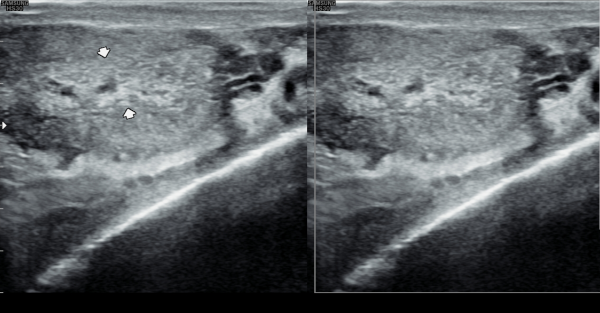

수십년간 빈뇨가 심해 비뇨기과에서 약만 투약하였으나 최근 2년전부터 급박뇨가 심해 내원 당일 검사한 경직장 전립선 초음파 검사상 항문 주위에 쌓인 탈락된

상피세포와 단백질등의 화학적 작용을 결석들이 생겨 항문 올림근등의 기능이 감소하여 급박뇨가 심해지고 있는 초음파 사진입니다.

This ultrasound image, taken during a transrectal prostate examination, shows small calcified deposits and accumulated epithelial cell debris around the anal area. These materials may have developed over time due to chronic inflammation and reduced circulation.

The deposits can affect the pelvic muscles, including the levator ani, leading to reduced muscle control and symptoms such as frequent urination and urgency. This finding helps explain the cause of the patient’s persistent urinary symptoms.